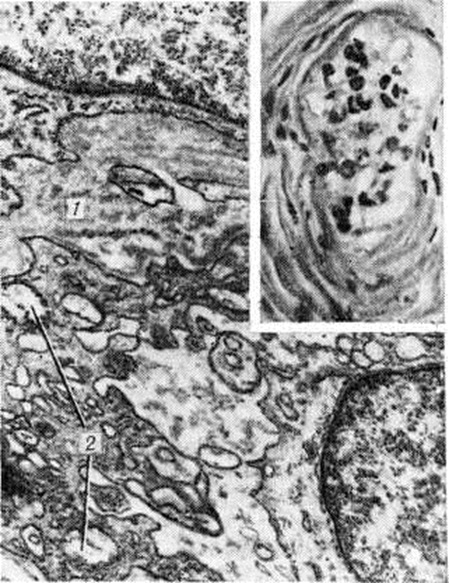

Рис. 1.

Флюоресцентные ангиоретинограммы: 1 — нормальное глазное дно (для сравнения); 2 — глазное дно больного сахарным диабетом с минроангиопатией сетчатки.

Поражение капилляров и венул состоит в утолщении их базальных мембран, повреждении, пролиферации эндотелия и перицитов и отложении в сосудах гликопротеидных веществ. Микроангиопатия особенно часто развивается в почках, сетчатке глаза (рисунок 1), коже (рисунок 3), мышцах и периневральных пространствах. Иногда она возникает раньше клин, проявлений Диабет сахарный и постепенно прогрессирует. При этом степень выраженности изменений микроциркуляторного русла определяется не столько длительностью Диабет сахарный, сколько степенью его компенсации при лечении. Повреждение, неравномерное утолщение базальных мембран, мукоидное набухание основного вещества сопровождаются нарушением сосудистой проницаемости. В эндотелии выявляется активный пиноцитоз (смотри полный свод знаний), альтерация и десквамация клеток. Реактивные изменения состоят в пролиферации эндотелия и перицитов, накоплении тучных клеток в периваскулярных пространствах. Синтез вещества базальных мембран эндотелием и перицитами, активация синтеза тропоколлагена приводят к необратимым изменениям в виде гиалиноза и склероза сосудов (рисунок 2).